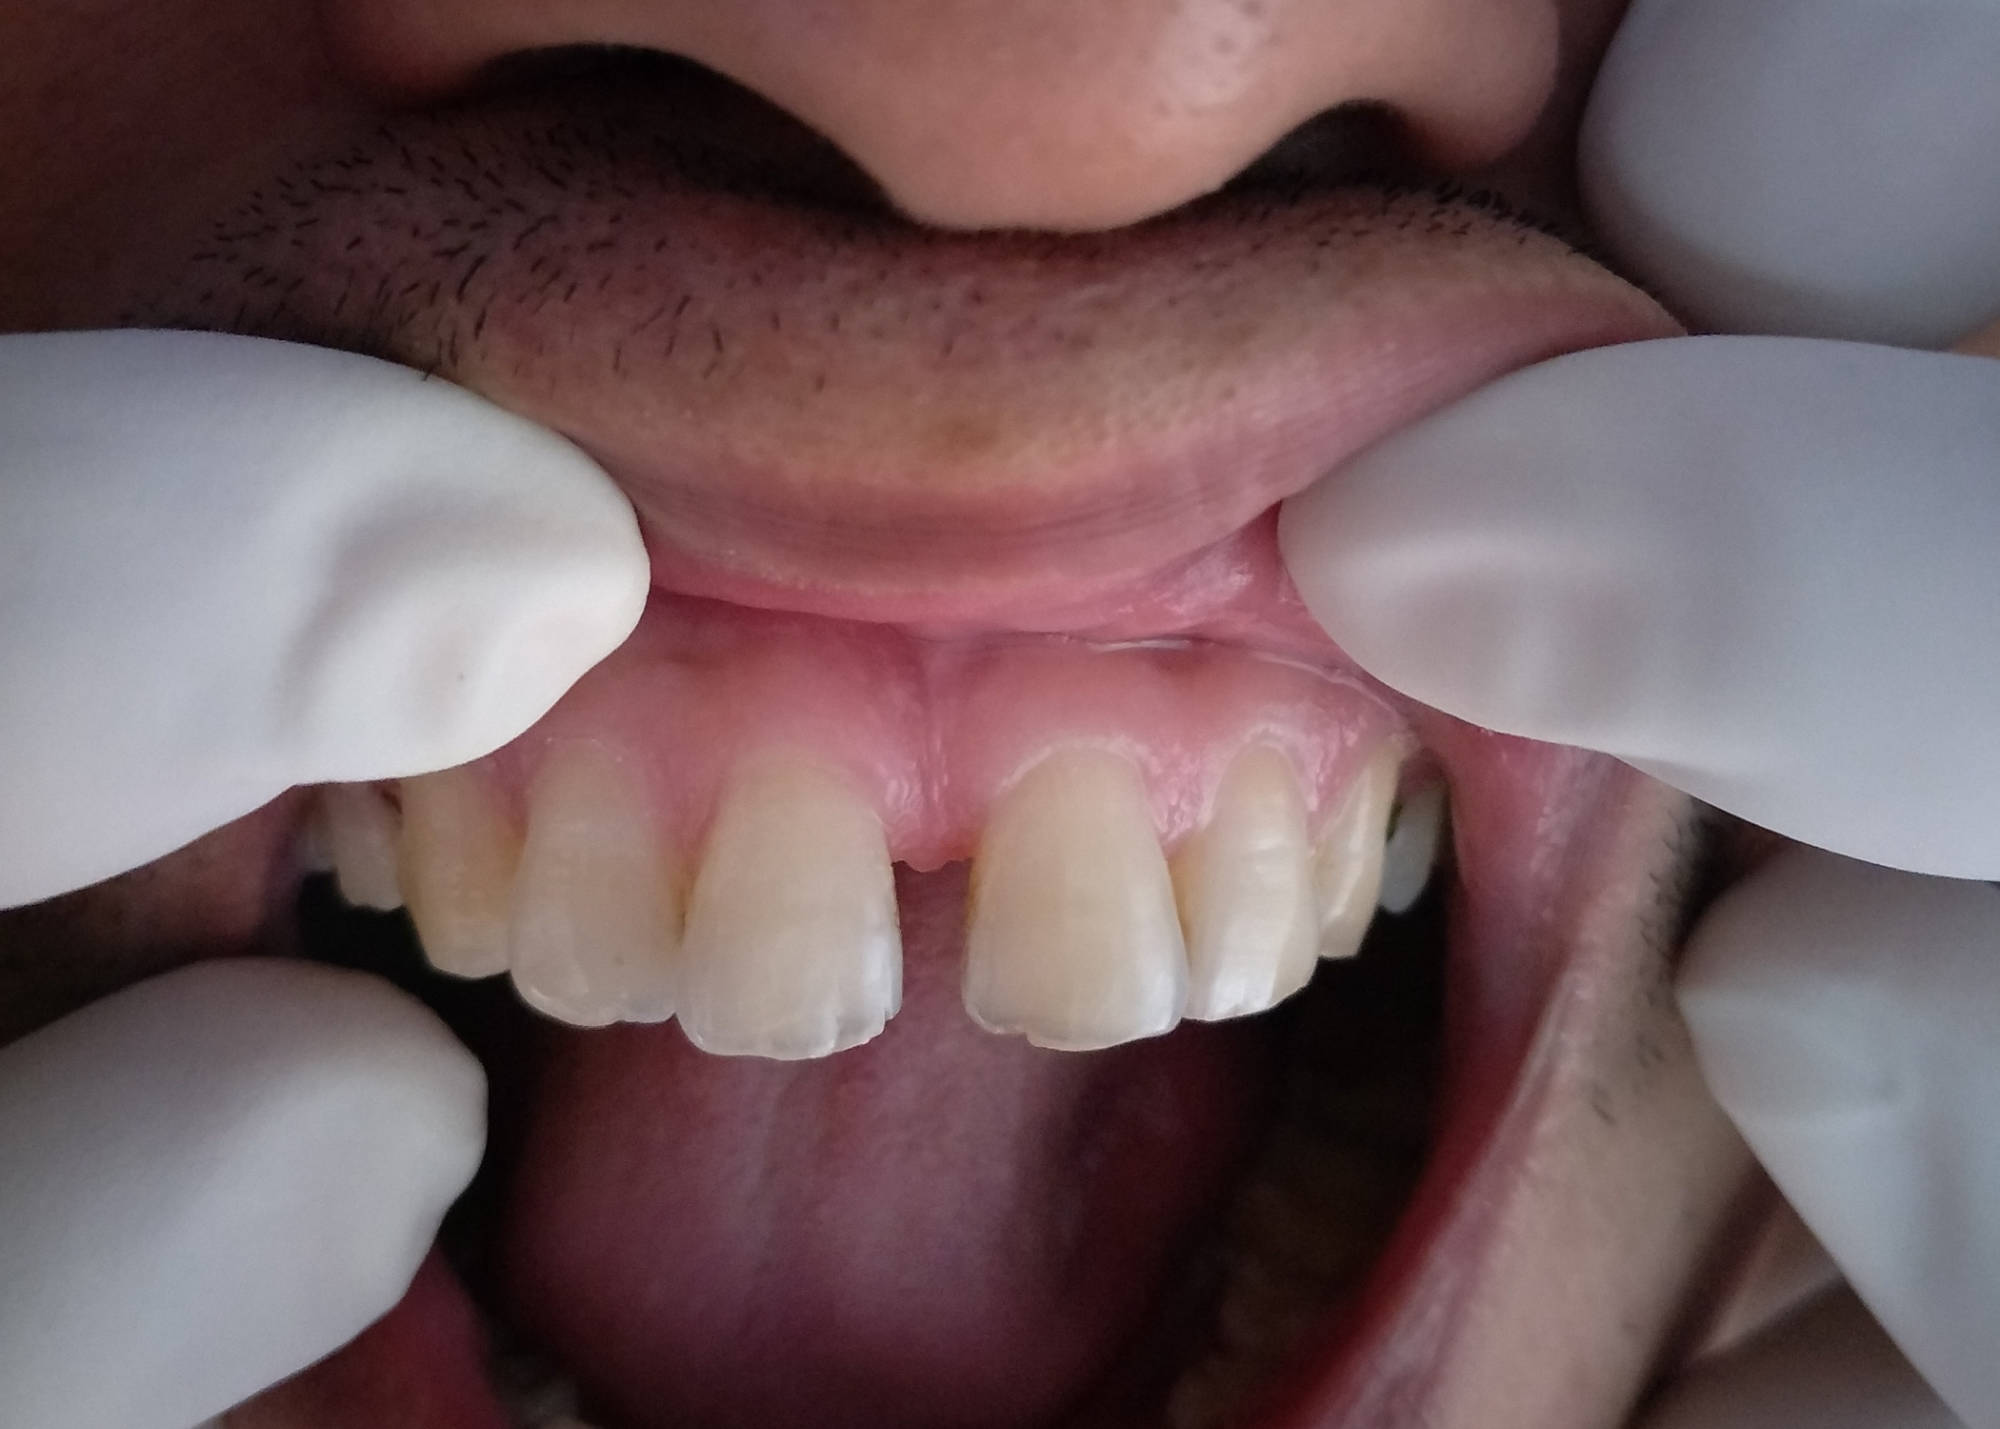

Collection of photos, here you will find the photos of doctor, services, environment and work.